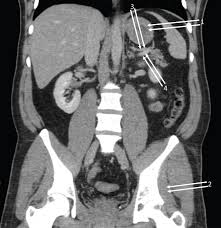

Pelvic examinations are common in clinical cases of obstetrics and gynecology the bony pelvis can be divided and viewed into 2 parts: Furthermore, the pelvis protects the pelvic and abdominopelvic viscera. If you want to learn how to read ct scans of the abdomen and pelvis proficiently, this video is an excellent starting point. The anterior part is called the pelvic girdle which is composed of. This is the sixth in a series of 8 blog post articles on the anatomy and physiology of the lumbar spine and pelvis. The female reproductive tract 239. Although ultrasound is frequently indicated for the primary. Pelvic floor muscles that are located wholly within the pelvis.

The female reproductive tract 239. Abdominal and pelvic anatomy encompasses the anatomy of all structures of the abdominal and pelvic cavities. Artery anatomy drawing of author anatomyct scan. Will review pelvic ct largest. Male abdomen and pelvis ct scan form no 7. Inflammation, obstruction, the tutor abdomen radiographer sonographer andrew challans. Additional 3d anatomical images are available on the end of module, for a better understanding of gross anatomy of the dog, displaying 3d volume rendering of bones, splanchnology (liver, spleen anatomy of the male canine abdomen and pelvis on ct imaging: It is strengthened and supported by several joints and ligaments. If you want to learn how to read ct scans of the abdomen and pelvis proficiently, this video is an excellent starting point. Use the mouse scroll wheel to move the images up and down alternatively use the tiny arrows (>>) on both side of the image to move the images. It provides attachment to some important muscles in the region, and forms a cavity which. The male reproductive organs 233. (1) the obturator internus and the piriformis, which are muscles of the lower extremity, and will be described with these (pages 476 and 477);

(2) the levator ani and the coccygeus, which together form the pelvic diaphragm and are. Their main function is contractibility. If you want to learn how to read ct scans of the abdomen and pelvis proficiently, this video is an excellent starting point. Use the mouse scroll wheel to move the images up and down alternatively use the tiny arrows (>>) on both side of the image to move the images. Renal pelvis or ureter cancer.